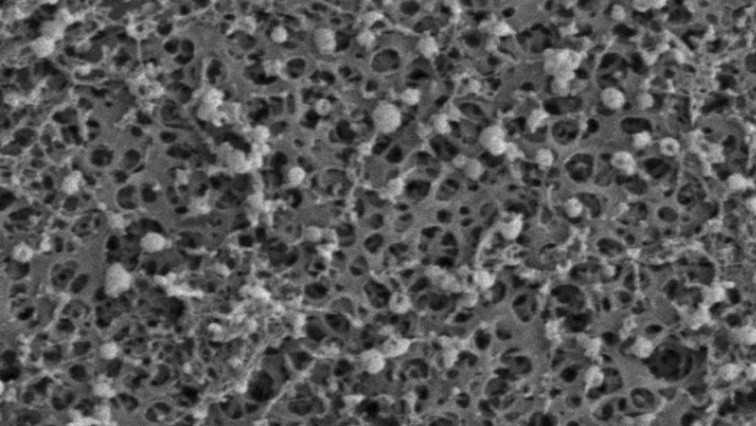

Extracellular Vesicles (EVs) are small particles that carry proteins, RNA, and other biomolecules from their cell of origin. They hold much promise for diagnostics and therapeutics, but isolating them from complex biofluids at high purity and throughput remains a major challenge. EVs are incredibly small - between 30 and 150 nanometers in size. To capture these tiny containers of messengers, scientists need to rely on sophisticated equipment such as ultracentrifuges. Unfortunately, these traditional methods of EV enrichment are time-consuming and resource-intensive with relatively low throughput.

Essential to the FAEVEr method is the use of Tween-20, a mild and inexpensive detergent added during EV washing steps. Its inclusion proved critical for improving the purity of the EV proteome by preventing fouling of the filter membranes used to trap EVs and by breaking weak interactions between EVs and contaminating abundant proteins. Importantly, this improvement in purity does not require complex chemistry or costly reagents, making the method accessible for both labs and clinical research settings using standard lab equipment.